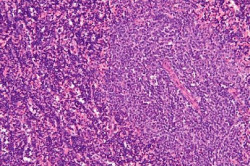

Un tratamiento experimental podría prevenir la metástasis `durmiendo` a las células cancerosas

Un nuevo enfoque terapéutico impide el crecimiento de tumores metastásicos en ratones al obligar a las células cancerosas a entrar en un estado de letargo en el que son incapaces de proliferar. El estudio, publicado en la revista `Journal of Experimental Medicine`, podría dar lugar a nuevos tratamientos que impidan la reaparición o propagación de varios tipos de cáncer, como el de mama y el carcinoma de células escamosas de cabeza y cuello (HNSCC).